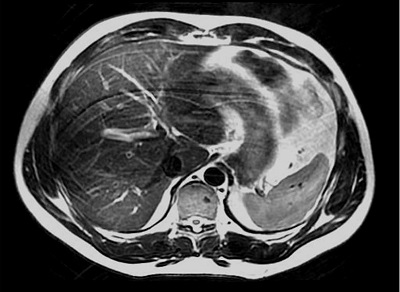

Figure 1. Axial abdomen with bands of signal cancellation (shading) due to incorrect patient positioning.

Shading artifacts, displaying as areas of reduced signal intensity or bands of signal cancellation, often result from improper coil or patient positioning.